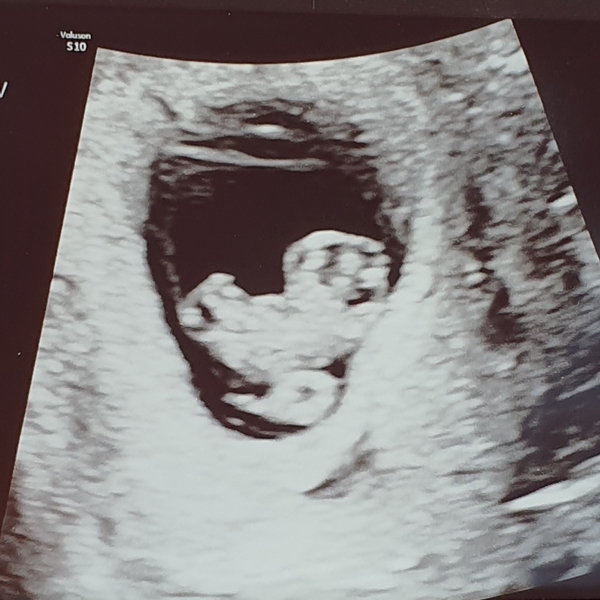

TwittleBee · 20/11/2019 07:55

Scan went well I guess! Very well to see baby looking healthy and a good heartbeat and right size etc. But not so good that the sac is measuring small and I'm bleeding still, can see the bleed on the scan. It's so small and they said it's common. But we were told we arent safe, I need to monitor my bleeding and if gets worse then head back in. Next scan in 3 weeks.

I'm really glad baby is looking healthy (love the scan picture!) but I'm sorry that news has been tainted with knowing that you still have a bleed that you need to monitor.

I have a guilty pleasure for watching Vlogs on Youtube. One of the mums I watch had a really tricky 1st trimester and lots of bleeds pretty much every time she walked anywhere, even shopping for food. But by her 12-week scan it cleared up and she now has a healthy 7-month-old girl. I really hope your bleed reabsorbs and stops bothering you.